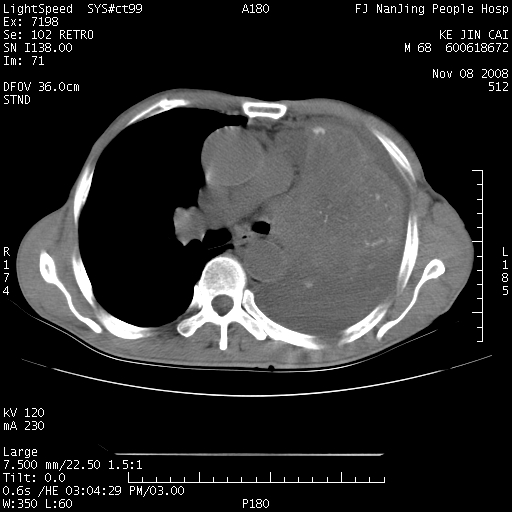

是个很有看头的病例,咋人气那么不旺?没多少人兴趣呢?这个病例几大怪:1   恶性肿瘤侵犯心肌左房怪,心肌一般不会被恶性肿瘤侵犯吧?2   左下肺均匀实变怪,内无含气,有别一般不张实变,含气肺泡完全为液体取代,而非一般不张实变的肺萎陷,冷不丁还以为是肿大的脾脏3   肿瘤本身怪,像tb肺不张4   这么有看头的病例没人气怪。呵呵。

追查病史,咳嗽,患者无发热,血象不高。据说2年前胸片检查怀疑肺ca曾行纤支镜检查,病理未见到癌细胞。无确切资料。

左肺恶性肿瘤侵犯肺动脉,左心房内瘤栓,胸膜转移。